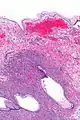

Micrograph showing a mucinous cystadenoma of the ovary. H&E stain. | |

Mucinous cystadenoma is a benign cystic tumor lined by a mucinous epithelium. It is a type of cystic adenoma (cystadenoma).